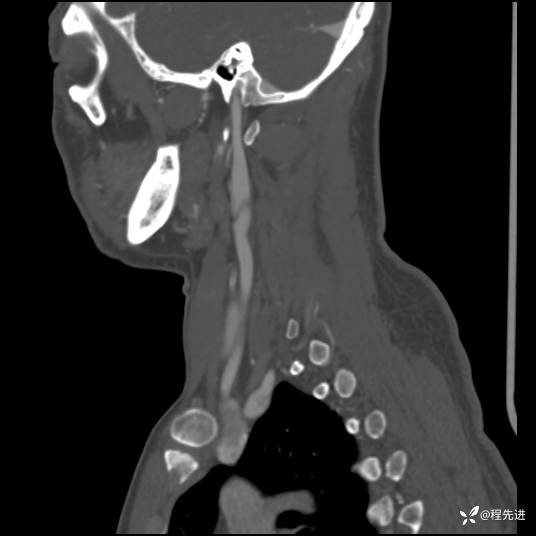

CT平扫+增强: